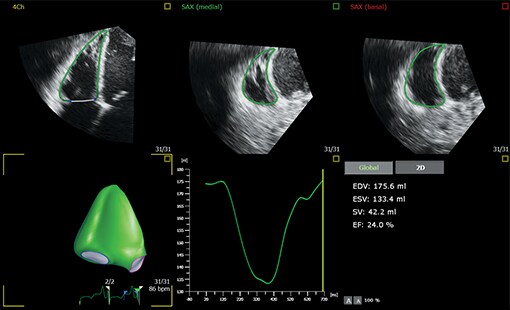

Evolving from Philips HeartModel, Dynamic HeartModel provides more critical capabilities in addition to LV and LA volumes to expand your clinical use and increase diagnostic confidence through 3D echocardiography technology. The Dynamic HeartModel tracks every frame over the cardiac cycle using 3D speckle technology. The moving contours of LA and LV borders and waveforms, additional LV, LA indexes and LV mass measurements provide a holistic view of the left heart function. The LV wall motion and the linkage between the LV and LA volume change over the heart cycle in order to increase your diagnostic confidence. In addition, the multi-beat selection and results average make the heart function evaluation more reliable than single beat, being ideal for arrhythmia or atrial fibrillation patients.

Boost your confidence in cardiac quantification during everyday workflows with HeartModel. This intuitive and validated 3D tool provides robust, reproducible ejection fraction (EF) in just seconds. What’s more, HeartModel is the only validated tool to provide simultaneous LV and LA volumes. It helps you easily characterize LA volume – shown to be an indicator of cardiovascular outcomes – to yield additional clinical information with no extra time or steps.